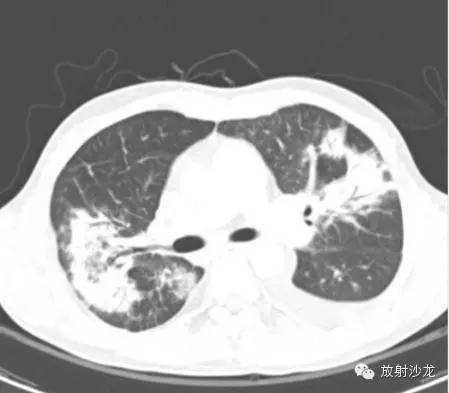

高剂量类固醇治疗三周后:

(第一次胸片示两肺中野及右肺下野多发斑片状高密度影。胸部CT示多发斑片状磨玻璃样密度增高影以及实变影,同时伴有小叶间隔的增厚。其中有些病灶部分表现为“铺路石征”。两周后CT随访显示这些病灶的密度和范围都增大。电视辅助胸腔镜肺活检下,活检标本病理诊断结果为急性纤维素性机化性肺炎。上述病变经高剂量糖皮质激素治疗三周后明显改善。)